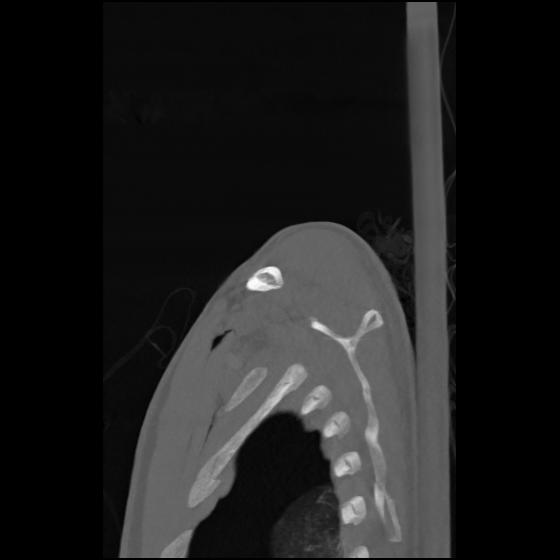

24 ANGIO,CE,Sag-MIP,5.000,ANGIO,Sag-MIP,